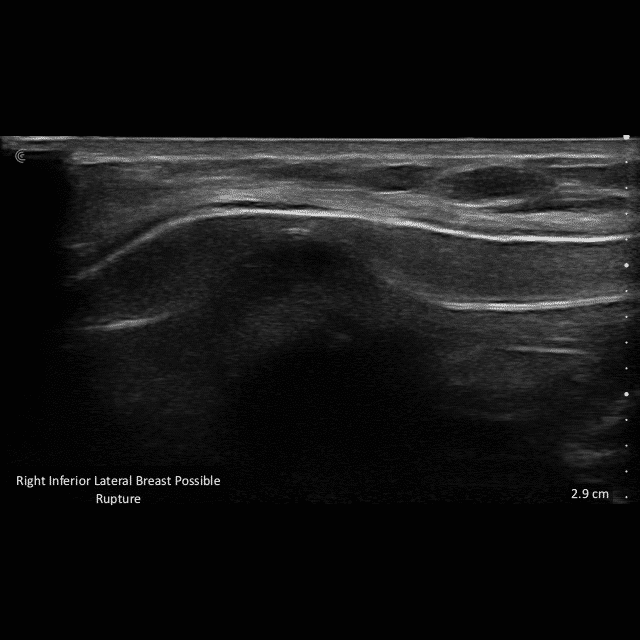

Ultrasound Imaging is very useful clinical tool to assess patient’s anatomy. In the past, ultrasound imaging was done primarily by radiologists, but is now being employed by many clinical specialties. Ultrasound use by Plastic Surgeons, however, is relatively new. Dr. Wigod has found ultrasound imaging to be a particularly valuable addition to physical exam and provides this service to his patients. Ultrasound imaging is especially useful to assess breast implants for problems such as ruptures, capsular contracture, and fluid collections. Dr. Wigod also uses ultrasound to examine other body areas and to help guide nerve blocks. Surgeon performed ultrasound does not replace radiologist performed imaging and is not for cancer screening.